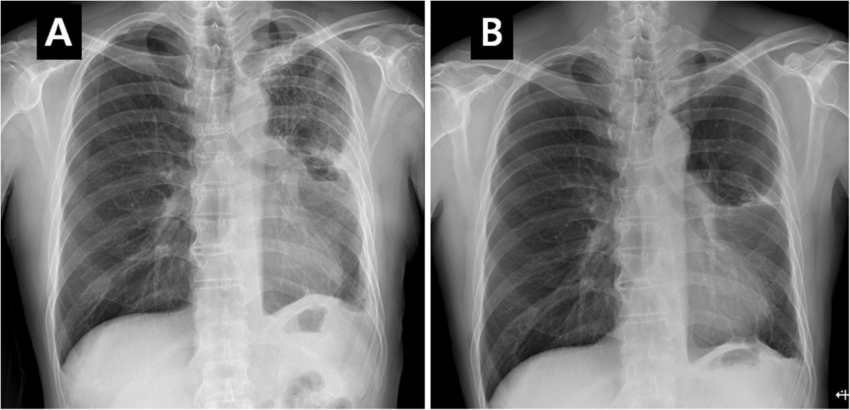

இனி நாம் குளோரின் வாயு எமது உடலில் ஏற்படுத்தும் தாக்கம் பற்றி பார்ப்போம். முக்கியமாக குளிரின் வாயு ஆனது எமது சுவாசத் தொகுதி மற்றும் கண் என்பவற்றினை தாக்கி கடுமையான எரிவினை ஏற்படுத்தும். மேலும் உடசுவாசிக்கும் பொழுது உட் சென்று நுரையிரலில் கடுமையான அலற்சியினை ஏற்படுத்தி உயிரிழப்பினை ஏற்படுத்தும். பாவிக்கும் குளோரின் ஆனது நீரினுள் சுயாதீனமாகவோ அல்லது அதனோடு இணைந்த உப்பாகவோ இருக்கும். கடுமையான வெப்பநிலை மற்றும் அளவுக்கு அதிகமான பாவனை என்பவற்றின் மூலம் குளோரின் வாயு நிலையில் நீர்ப்பரப்பின் மேல் இருக்கும். இவ்வாறு இருக்கும் வாயு ஆனது சுவாசம் மூலம் மனிதனை அடையும் இதனால் அவர்கள் கடுமையான இருமல், தொண்டை நோ, சுவாசிக்க கடினமான தன்மை என்பவற்றினால் அவதியுறுவர். மேலும் நுரையிரலில் pneumonitis என்ற கடுமையான அலற்சியினை ஏற்படுத்தி உயிரிழப்பினை ஏற்படுத்தும்.